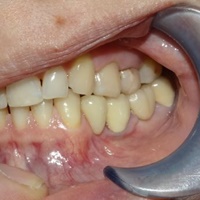

Odbudowa kosci wyrostka zębodołowego żuchwy, odbudowa dziąsła, wydłużenie koron klinicznych górnych przedtrzonowców, implantacja.